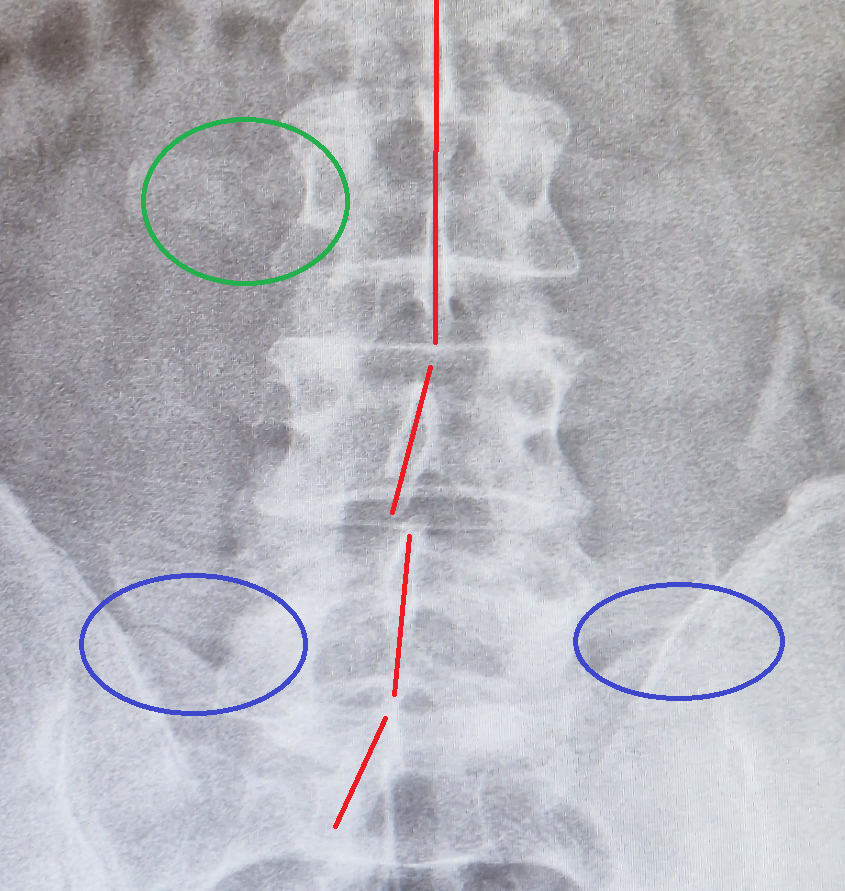

Ich würde sagen, der Bub hat beim Knipsen schief gestanden / gelegen, ev. wegen Schonhaltung, sieht man am Beckenschiefstand (blau).

Da ist es auch tatsächlich an den unteren Lendenwirbeln bissi schief (rote Linie).

Und eine Rippe hat oder hatte mal etwas abgekommen. Ev. eine alte Verletzung (grün).

Also im Sterben scheinste nicht zu liegen, ich (nicht Andere) würde mal noch 3-4 Tage abwarten, wenn es keine Besserung gibt, kommt Plan B oder C.